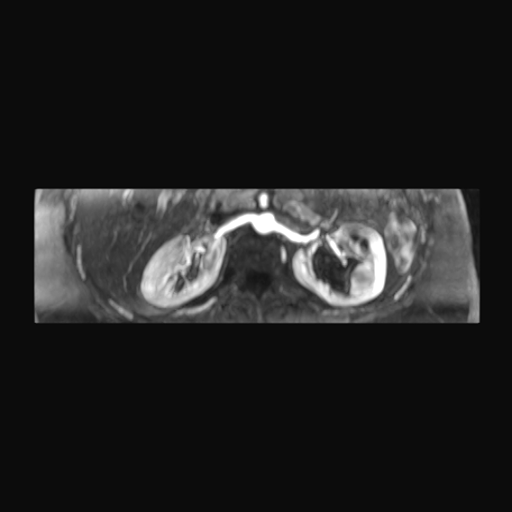

Paciente de sexo femenino, de 45 años de edad, refiere infecciones urinarias a repetición, no hay dolor, no refiere trauma, consulta por ardor al orinar, medico tratante le solicita resonancia abdominal, con énfasis en riñones, además un estudio de angiorenal.

Se prepara a paciente para ingreso a zona 4 del área de resonancia. Se coloca a paciente en decúbito supino, se canaliza en vena antecubital, se utiliza bobina de abdomen de 16 canales, se adquieren localizadores en tres planos, luego se procede a adquirir imágenes en diferentes planos, con secuencias echo spin y eco de gradiente, potenciadas a T1 y a T2.

Los sistemas colectores del riñón derecho y del riñón izquierdo, muestran alteración de sus calices primarios y secundarios, mostrando dilatación, la pelvis renal y el uréter se observan de características normales lo que indica que no hay proceso obstructivo.

Se observa dilatación del sistema calicial sin proceso obstructivo compatible con una anormalidad del desarrollo de los sistemas colectores de ambos riñones, definiéndose como una “megacaliosis”